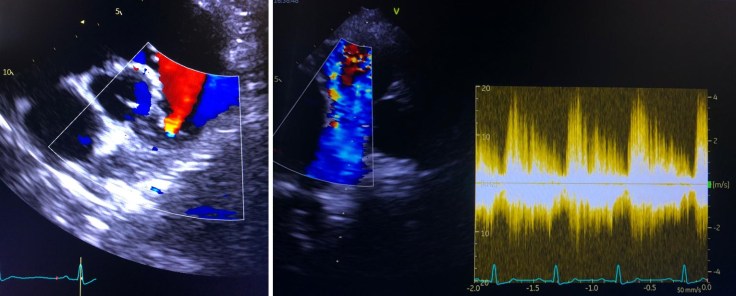

Per tale motivo l’esame idoneo a capirne l’origine è l’esame ecocardiografico. È un esame di durata variabile tra i 40 ed i 60 minuti, che solitamente si effettua sul cane sveglio, sdraiato su un apposito tavolino e permette di valutare il flusso sanguigno e i tessuti del cuore. A questo esame, su indicazione del Medico Veterinario che esegue la visita di approfondimento cardiologico, fa seguito un esame elettrocardiografico (comunemente chiamato ECG), per valutare la funzionalità elettrica del muscolo cardiaco e la presenza di eventuali aritmie concomitanti.